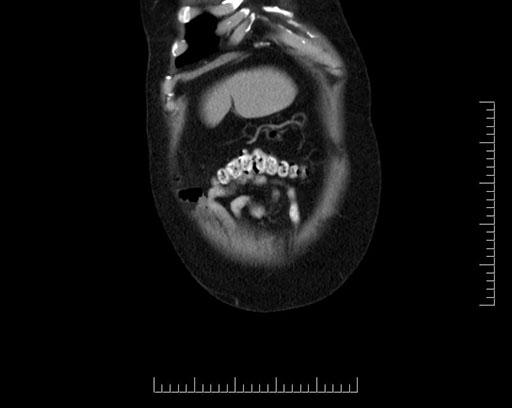

Axial - 3 months prior